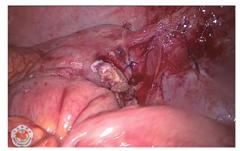

患者女,40岁,身高160 cm,体质量52 kg,因2 d前无明显诱因出现左下腹部持续性绞痛,于2018年10月19日急诊入院,体温37.7℃,脉搏112次/分,伴稍恶心,无呕吐、放射痛、发热,无腹泻、血便,无尿频、尿痛等症状。1 d前曾在当地社区医院以"急性肠炎"给予抗感染、解痉等治疗,自觉症状有所缓解,次日午间症状再次加重。查体:左下腹压痛(+)、反跳痛(+),局部腹肌紧张明显。行腹部CT平扫检查示:结肠走行反位,右半结肠位于左上腹,阑尾增粗伴周围渗出,周围间隙模糊,阑尾最粗约1.7 cm,临近盲肠壁稍增厚;胃腔大部分位于右侧,十二指肠垂直下行,可见Ladd束带;肝脏体积明显增大;脾脏受推挤,位于左侧肾上腺前方(图1,图2,图3)。诊断为"结肠反位,阑尾炎累及盲肠"。血常规检查示:白细胞计数8.81×109/L,中性粒细胞百分比79.5%。综合各项检查结果,诊断为"急性肠旋转不良型左侧阑尾炎",遂于当夜急诊行腹腔镜下异位阑尾切除术。腔镜探查示盆腔内大量积脓,大网膜覆盖左侧回盲部,乙状结肠位于盆腔右侧,肝左叶明显增大并覆盖脾脏,胆囊仍位于右侧,切除阑尾及网膜组织大小约8.0 cm×6.0 cm×2.5 cm(图4,图5,图6,图7)。

腹腔镜手术或开腹探查手术是治疗左侧阑尾炎的主要方式。由于术前已考虑为左侧阑尾炎,故腔镜Trocar放置位置为常规位置的镜像旋转,脐上置10 mm Trocar,右侧腹壁及右下腹壁分别置入5 mm及12 mm Trocar,为方便右手操作以he-mo-lock夹夹闭阑尾根部,右下腹麦氏点所置Trocar为12 mm,其他手术操作过程与常规腹腔镜下阑尾切除术无异。